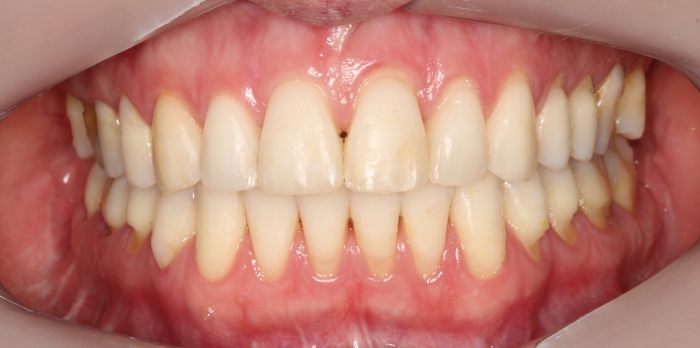

Mordida inicial

Oclusão após a cirurgia